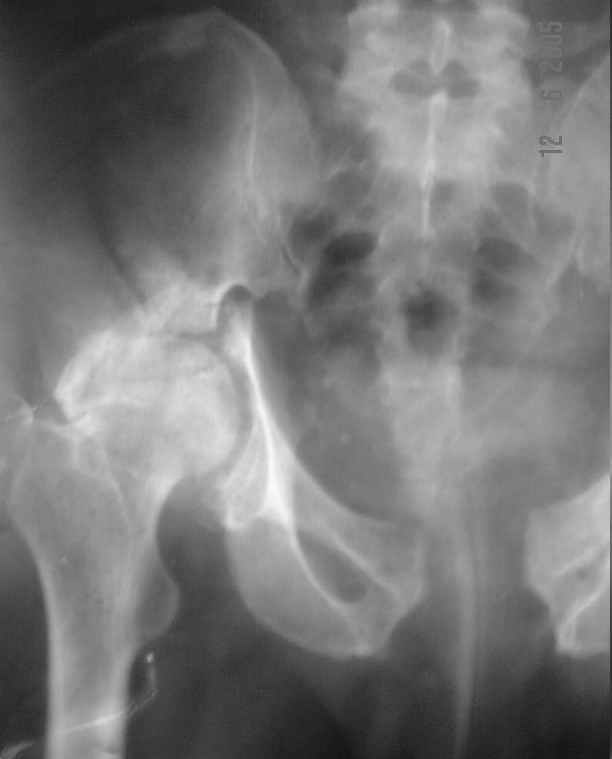

Dear All, The patient came to us for opinion regarding this # of pelvis which he sustained 5 months back.

He gives history of being on skin traction for 3,5months. After that he was advised partial weight bearing to be graduated to full weight bearing. Now the patient has difficulty in weight bearing as it is painful. He can walk a few steps only with the help of a walker. Hip movements are restricted and painful. Fl-90* ER-10* IR-0, shortening-4cm. He also had # of humerus and radius/ulna, which were plated and have united. The serial x-rays of the pelvis/Hip during these 5 months show that the hip joint has been in the same position. I have the CT pictures also but not digitalized as yet.

It is a displaced and ununited fracture of the acetabulum, probably type C (AO). The pelvis is not fractured from what one can see of the sacro iliac joint.

That is why the hip movements are restricted.